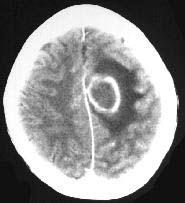

成年男性,头疼、头胀、发热,血象高,CT检查如图,选择最可能的诊断()A.脑脓肿B.胶质瘤C.皮样囊肿D.脑梗死E.脑膜瘤

问题 成年男性,头疼、头胀、发热,血象高,CT检查如图,选择最可能的诊断()

选项 A.脑脓肿 B.胶质瘤 C.皮样囊肿 D.脑梗死 E.脑膜瘤

答案 A